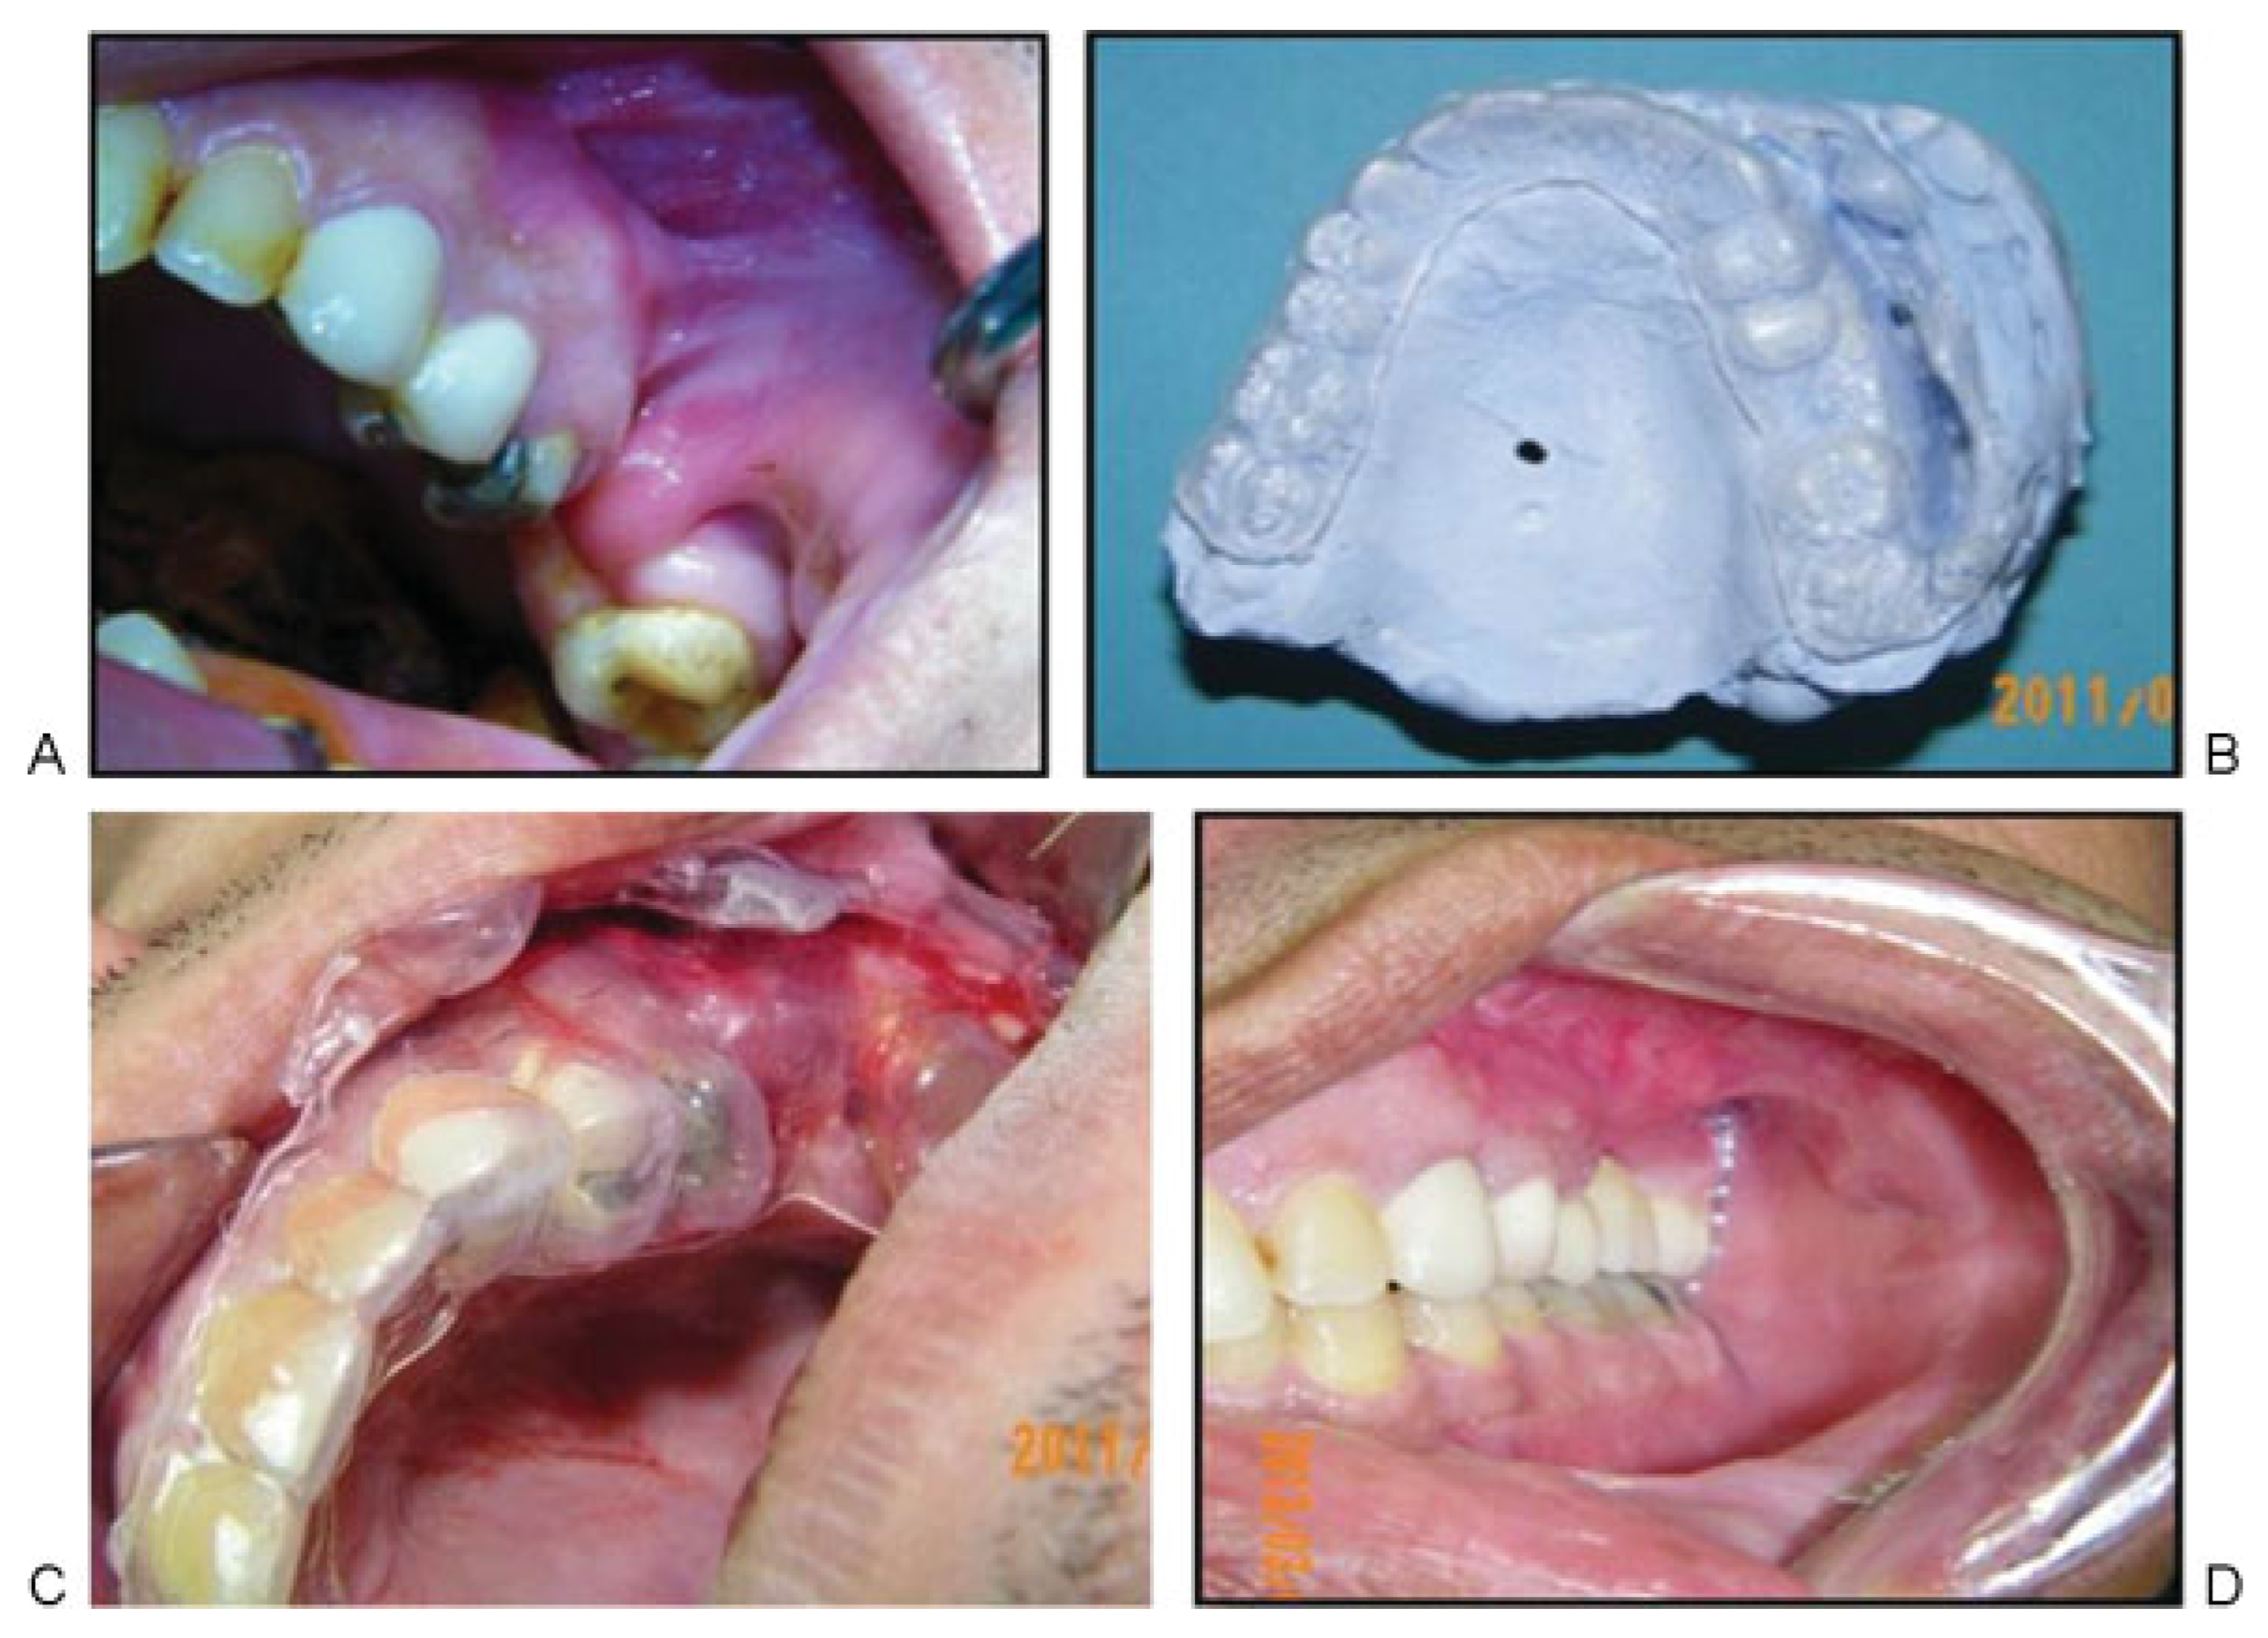

Figure 2. (A) Preoperative view of cheek adhesion with vestibular loss and restricted mobility. (B) TV stent adapted to the model note; the holes at the vestibular depth. (C) Thermoplastic vestibuloplasty stent allows creation of vestibule and prevents adhesion without additional retention. (D) Three months postoperative showing excellent vestibular depth, normal mobility color and texture.

Ten patients suffering from vestibular loss and adhesion that varied from anterior lip (Figure 1A,B) to posterior cheek area (Figure 2A,B) were included with all data summarized in Table 1. All patients received a thorough explanation of the procedure and then signed a written informed consent before enrollment.

Under general anesthesia, the adherent area was sharply deepened to the preplanned vestibular dimension. Then, the prefabricated sheet was freely seated on place and any interfering tissues were carefully removed. The sheet periphery, which is inherently curved to 180 degrees, was sutured to the lip to prevent any stent movements Figure 1C,D and Figure 2C). Lip mobility was carefully checked and the patients were kept on soft diet and rigid cleaning protocol. Two weeks later, sutures were removed, stent was cleaned, and the patients were instructed to wear it continuously for another 2 weeks except during eating and cleaning.

All the patients tolerated the procedures uneventfully. Minor complaints were reported in the first 2 weeks. Most of them resolved following suture removal including bad odor, difficulty in eating, and cleaning. The mean vestibule length significantly increased by 205% at 15 days postoperatively (p < 0.001) (Figure 1E), then it slightly decreased by (−14%) after 3 months with an overall increase of 163% (p < 0.001) (Table 2, Figure 3). While the mean mobility score significantly increased from 0.3 preoperatively to 1.6 and 2 at 15 days and 3 months, respectively (100%) (p < 0.001) (Figure 1F and Figure 2D). Moreover, the total VAS score significantly increased from 25.3 preoperatively to 38.1 (54%) and 50 (103%) at 15 days and 3 months, respectively (p < 0.001).